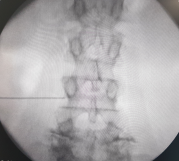

The degenerative curve develops due to asymmetrical/ unequal wear and tear changes in the discs of lumbar spine, leading to bending and rotation of the spine to one side. Sometimes, the scoliosis (sideward curve in the spine) might have existed from childhood and the degenerative changes in the older age lead to worsening of the curve and start off the symptoms. The curve tends to progress with time and symptoms worsen accordingly.

Treatment depends on the severity and nature of symptoms, spinal balance, limitation of daily living activities and the findings on the X-rays and the MRI of the spine. Medication for pain control, physiotherapy and exercises are helpful in most of the patients. Some patients may be advised injections to the spine for relieving back or leg pain. Injections give a temporary relief and help in starting the exercises and reduce the need for pain medication. Sometimes the injections are used as a test to decipher the pain generator or the segment that is predominantly responsible for the symptoms.

Surgical treatment is necessary in some of the patients with degenerative scoliosis with severe symptoms, loss of spinal balance and restricted lifestyle due to back or leg pain. Surgery may range from a single level decompression of nerve roots to a multiple level fixation and fusion of the spine with implants to correct the deformity and improve the spinal balance.